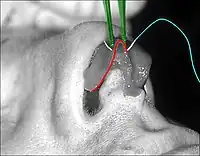

Rhinoplasty: The lower lateral cartilage (greater alar cartilage) exposed for plastic modification via the left nostril. | |

- Photograph 1. – Open rhinoplasty: The incisions are endonasal (in the nose), and thus are hidden. The skin-incision to the columella aids the plastic surgeon in precisely suturing to hide the scar—except for the columellar incision (red-dot guideline) across the nasal base. The columellar incision allows the surgeon to view the size, shape, and condition of the nasal cartilages and bones to be corrected.

- Photograph 2. – Open rhinoplasty: The nasal interior. The scissors indicate the lower lateral cartilage (blue), which is one of the wing-shaped cartilages that conform the tip of the nose. The jagged red delineation indicates the locale of the columellar incision. Once the skin has been lifted from the bone-and-cartilage framework, the surgeon performs the nasal correction tasks.

- Photograph 3. – Open rhinoplasty: To narrow the tip of a too-wide nose, the surgeon first determines the cause of the excess nasal width. The suture being emplaced will narrow the tip of the nose. The red delineation indicates the edge of the nose-tip cartilage, which is narrowed when the surgeon tightens the folded cartilage apex. The suture (light blue) ends in the needle (white); tweezers (green) hold the nasal cartilage in place for the suturing.

- Photograph 4. – Nasal hump excision: The black delineation indicates the desired nose-reduction outcome: a straight nose. The nasal hump is bone (red) above the scalloped grey line, and cartilage (blue) below the scalloped grey line. The surgeon cuts the cartilage portion of the hump with a scalpel, and chisels the bone portion with an osteotome (bone chisel). After chiselling away the main mass of the nasal hump with an osteotome, the surgeon then sculpts, refines, and smoothens the cut nasal bones with rasps (files).